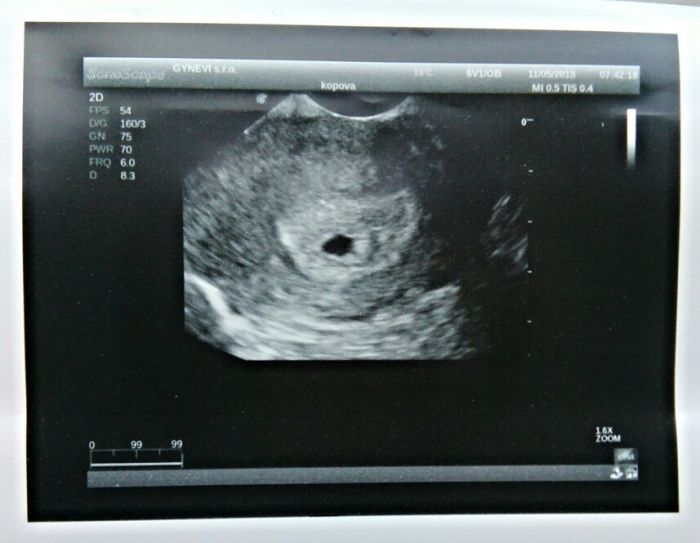

Ahojky holky,tak první prohlídka za mnou.Těhotenství potvrzeno utz,jsem 5+3tt,říkal dr.že je tam,na správným místě a správně roste!!Pracovat můžu normálně dál,jen abych netahala těžší věci nad cca 10kg...takže prej bych mohla chodit až do konce smlouvy,což mě hodně potěšil

Další kontrolu mám 1.6.kdy bude velký utz,a koncem června vypíšeme těhu průkaz.Doporučil mi vitamíny Chytré miminko,tak jsem si je u něj hned koupila

Přidávám fotečku fazolky